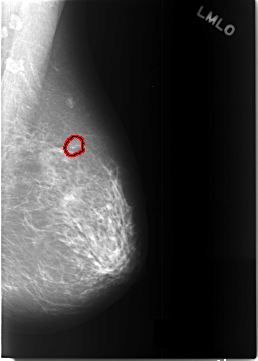

C_0449_1.RIGHT_MLO

LEFT_MLO LINES 5768 PIXELS_PER_LINE 4120 BITS_PER_PIXEL 12 RESOLUTION 50 OVERLAY

FILE: C_0449_1.LEFT_MLO.OVERLAY

TOTAL_ABNORMALITIES 1

ABNORMALITY 1

LESION_TYPE CALCIFICATION TYPE DYSTROPHIC DISTRIBUTION CLUSTERED

ASSESSMENT 4

SUBTLETY 5

PATHOLOGY BENIGN_WITHOUT_CALLBACK

TOTAL_OUTLINES 1

BOUNDARY